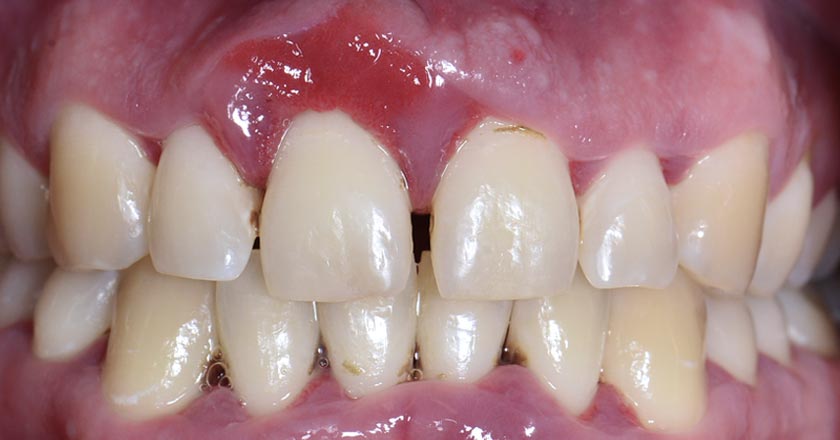

Gum Disease - Before And After